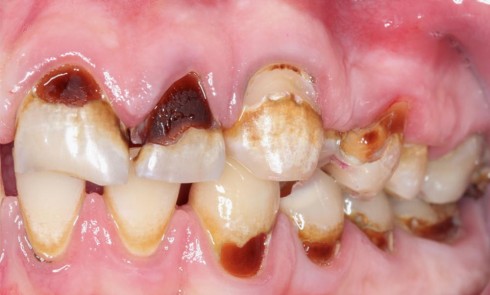

Article réservé à nos abonnés Prise en charge occluso-prothétique des conséquences orales et maxillo-faciales du bruxisme : apport de la prothèse amovible de recouvrement

Le bruxisme est défini comme le grincement parafonctionnel des dents, ou encore comme une habitude orale composée de tapotements, de...